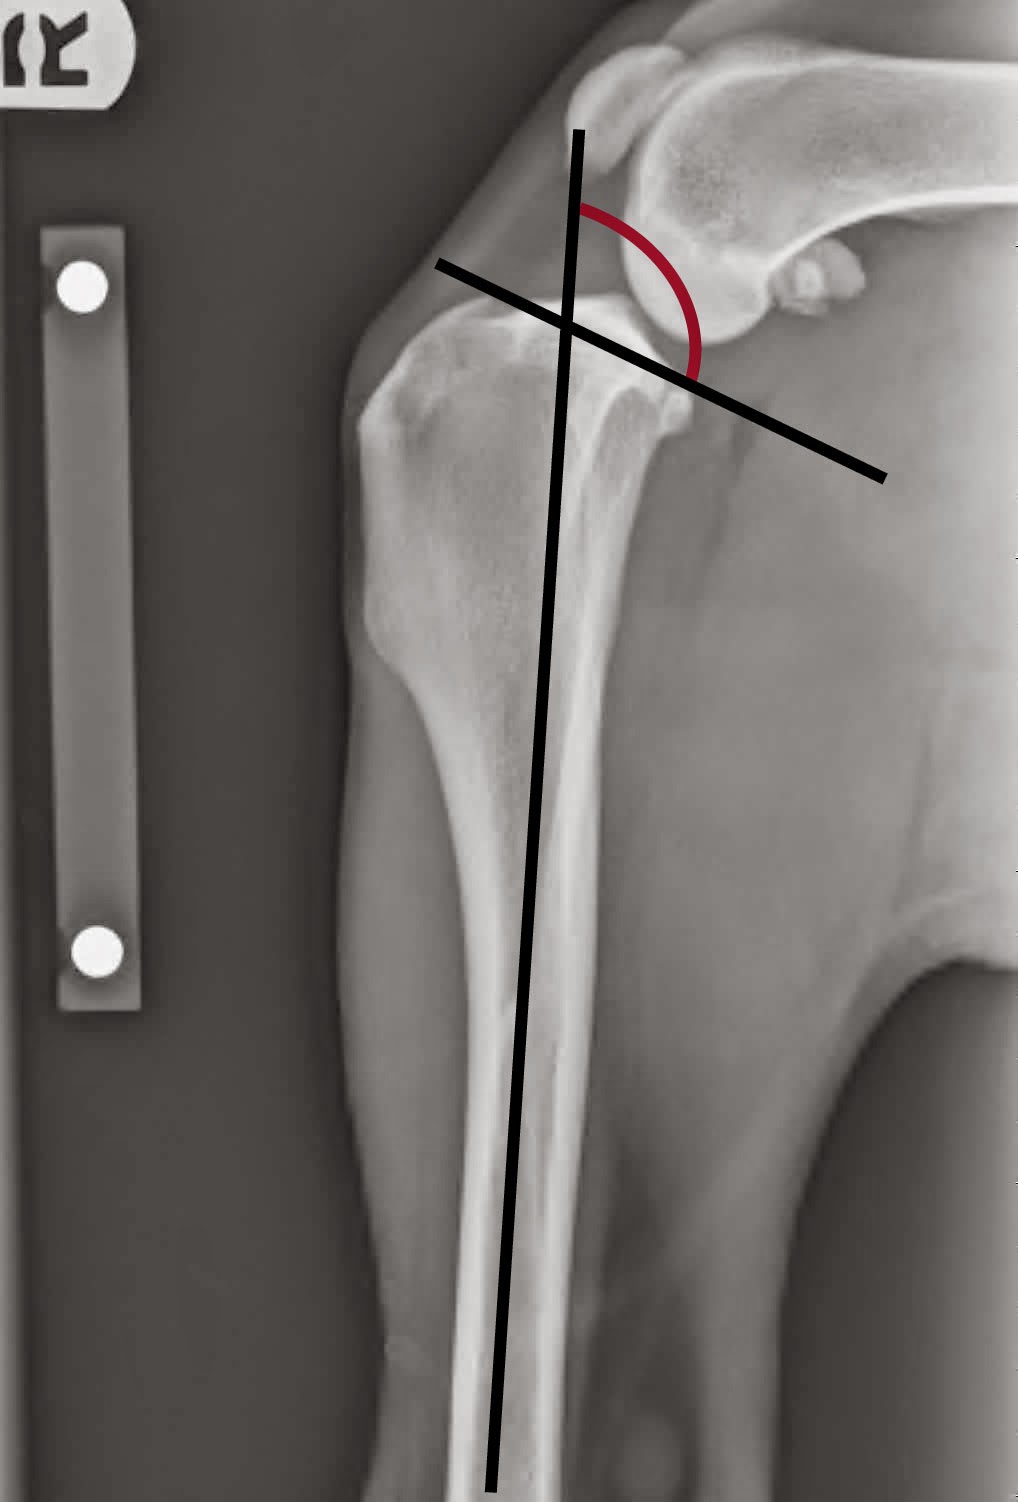

tplo Postoperative view of a TPLO procedure from the front Tplo Surgery After Care a tibial plateau leveling osteotomy (tplo) is one of several potential surgical procedures to repair a torn acl in dogs. so the best option is to do things right the first time around during the initial tplo surgery recovery time, so the. after your dog undergoes tplo surgery, the first week of recovery is crucial. It's a. Tplo Surgery After Care.

tplo Postoperative view of a TPLO Veterinary Surgical Specialists Tplo Surgery After Care a tibial plateau leveling osteotomy (tplo) is one of several potential surgical procedures to repair a torn acl in dogs. Tplo surgery recovery week by week requires patience, commitment, and attentive care. though your pet may feel ready to return to activity soon after surgery, appropriate activity restriction is critical for proper canine tplo. the development of. Tplo Surgery After Care.